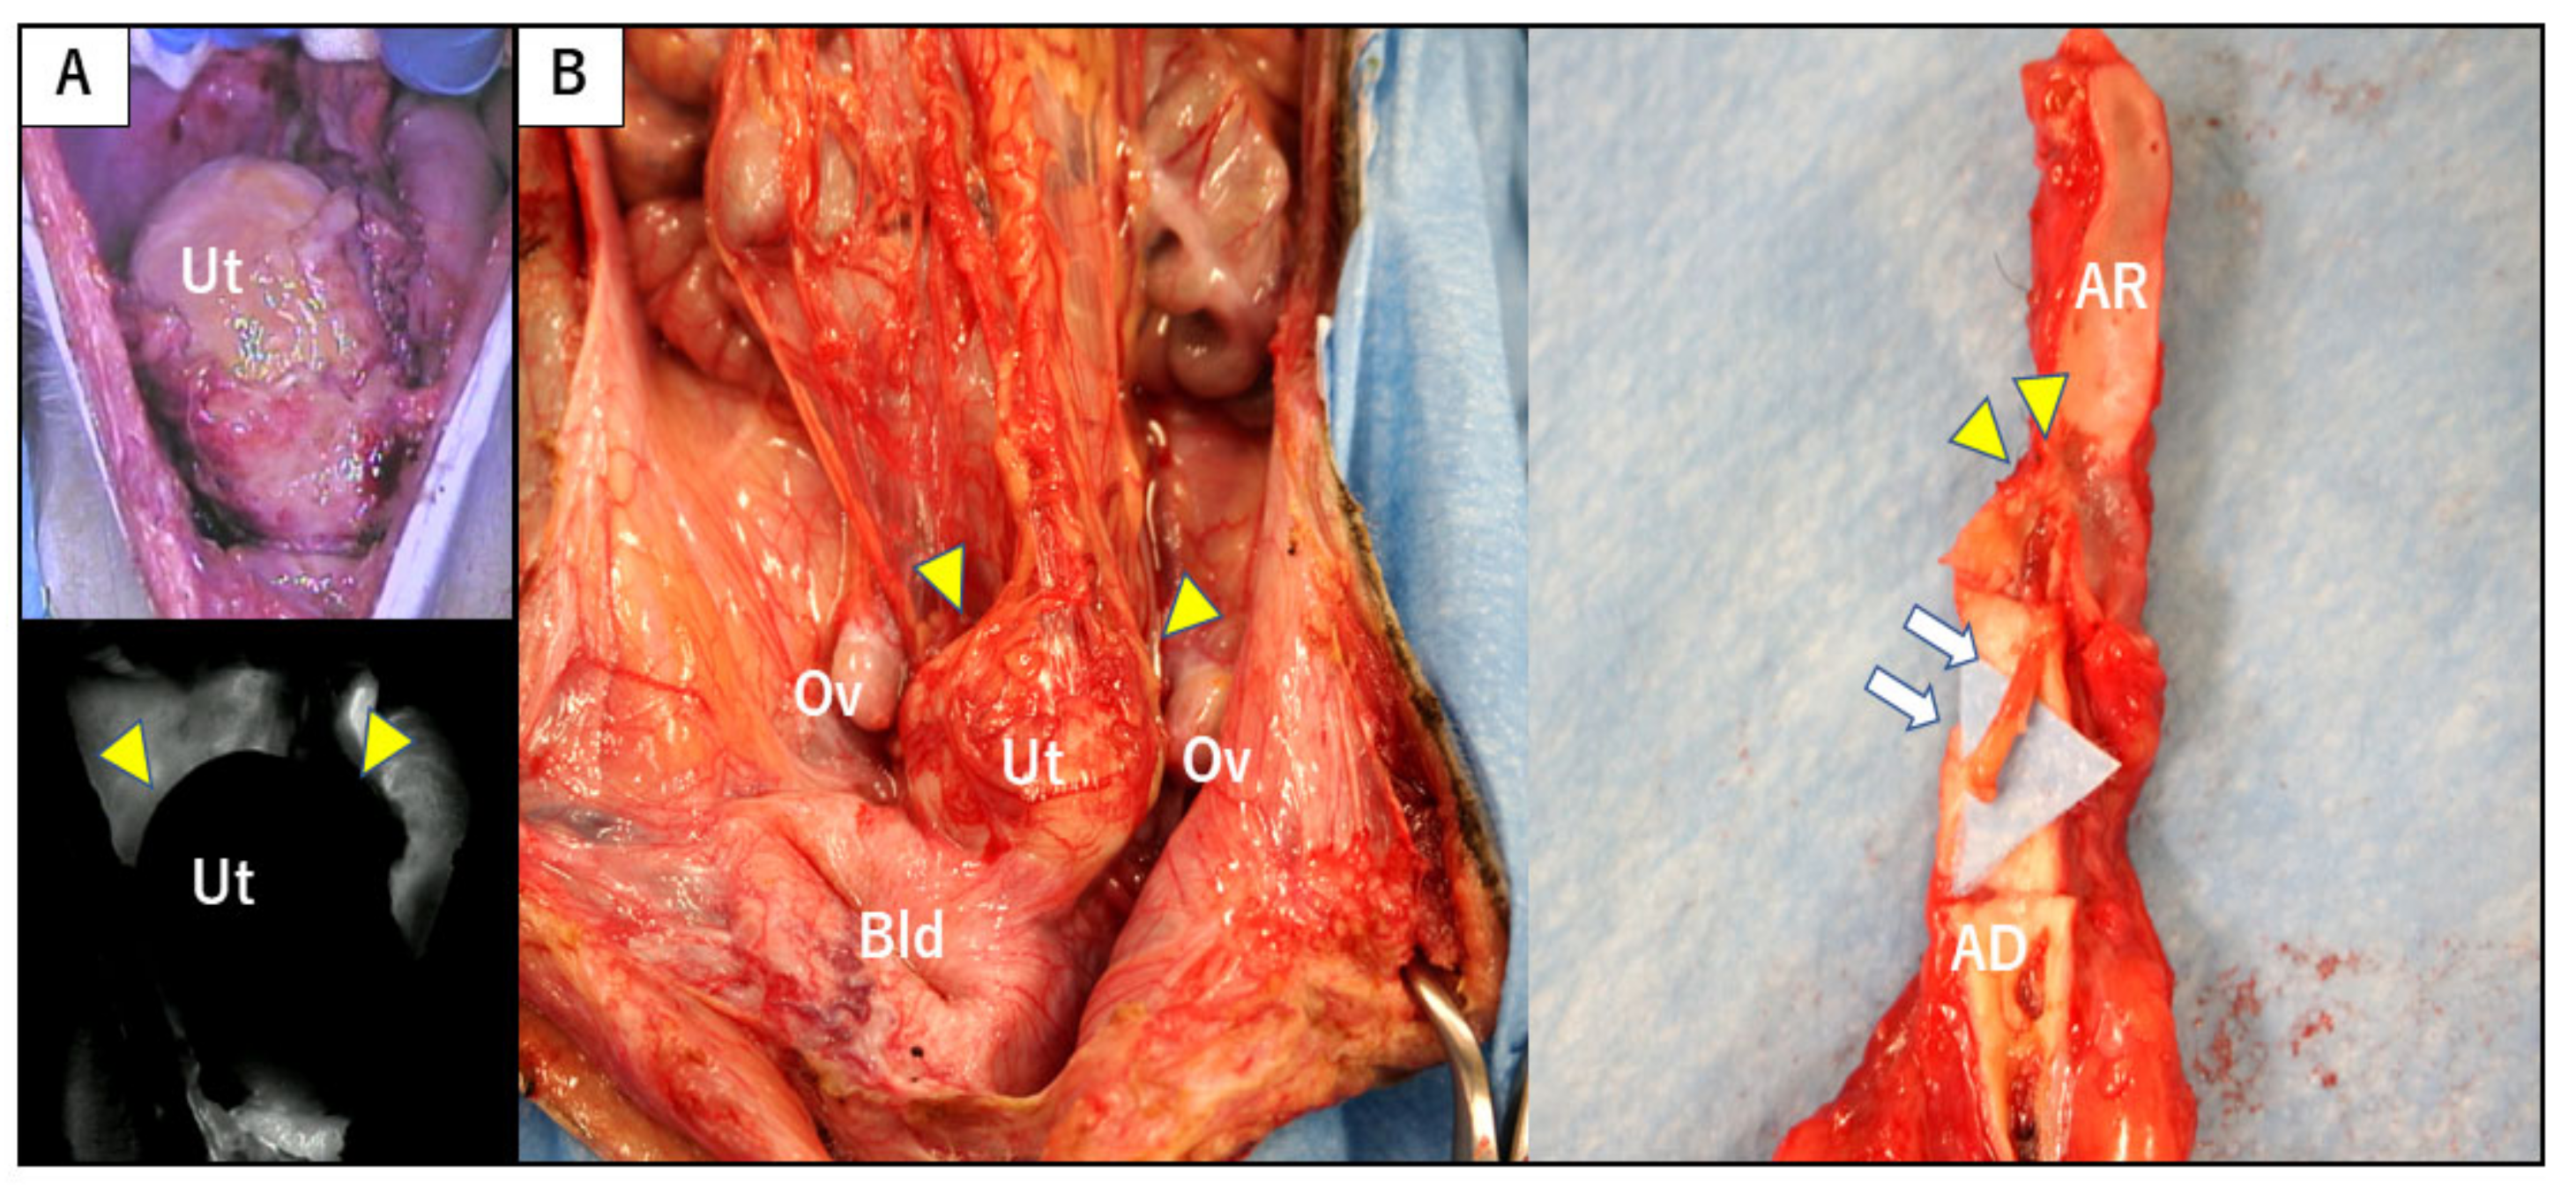

3.1. Surgical Outcomes of Uterus Transplantation

3.6. Pregnancy and Delivery